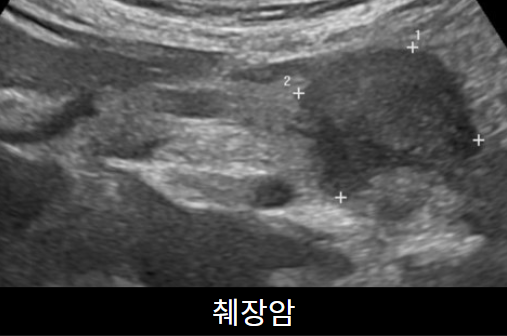

가장 많이 하는 초음파입니다. 간,담낭, 총담관, 췌장, 비장, 신장을 검사합니다. 지방간, 간경화, 간암, 혈관종, 담낭돌, 담낭용종, 췌장염 등을 진단할 수 있습니다.  약 10분 정도 소요되며 다른 검사와 달리 8시간의 공복이 필요합니다.